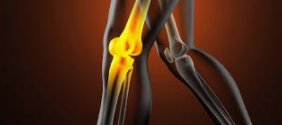

| 무릎 물참 원인

무릎 물참 원인은 앞서 이야기 했듯이 무릎에 염증이 생겼기 때문인데, 무릎 주위 근육 및 인대에 손상이 발생되어 나타나는것이 대부분 입니다. 이러한 경우에는 간단하게 손으로 눌러 어느 위치에 염증이 났는지 쉽게 알 수 있습니다.